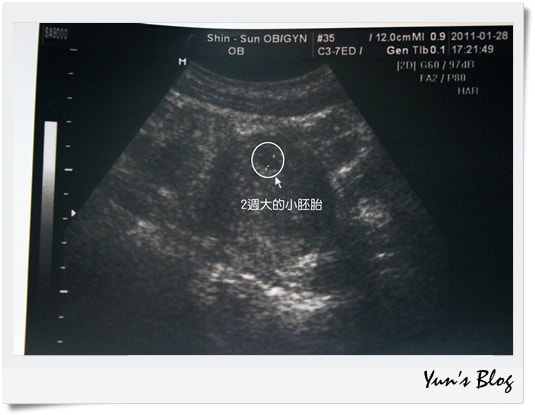

2週大的小胚胎,只有0.65公分左右,還真的是小胚胎耶!

小到幾乎看不到、像一個碗豆的形狀,

實在很難想像,這個小東西會慢慢長大,

然後變成一個人,有頭、有身體、有手、有腳、有思想,

光是想像就覺得好神奇喔!

喜悅之餘,我卻忽然擔心起來,

前陣子不知道懷孕了,

我感冒還是照樣吃藥、我照樣跳肚皮舞、有氧舞蹈、踩飛輪,

因為僵直性脊椎炎的關係,我也長期在吃消炎止痛藥,

怎麼辦?會影響寶寶嗎?

醫生告訴我,

只要胚胎會長大,就表示早期吃的藥做的事,通通都沒有影響,

如果有影響,小胚胎就會停止生長,不會有心跳。

這樣聽起來,我更擔心了,

怎麼辦?還要再等2週才可以測到心跳,

如果2週後沒有心跳,那不就是我害的嗎?

如果2週後沒有心跳,那不就代表要拿掉嗎?

我才不要!

這一刻我也終於明白,

原來當媽媽,是從確定懷孕的那天起,就對孩子有了無窮無盡的擔心。